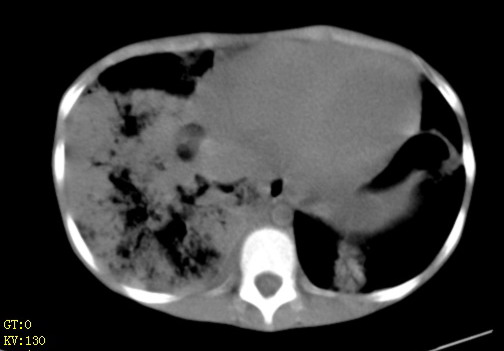

先心(室缺?)、左室大,心功能不全;肺部感染

1、左心房、左心室增大,考虑左心衰, 2、肺水肿合并感染 3、双侧胸腔积液

双肺中下野不规则片絮状阴影,中外带明显,双侧胸腔少量积液,心影增大,心腔密度减低,隆突下及左侧气管旁见钙化淋巴结影,考虑双肺感染、心衰;建议结合临床除外h1n1并急性心衰,先心不能排除。